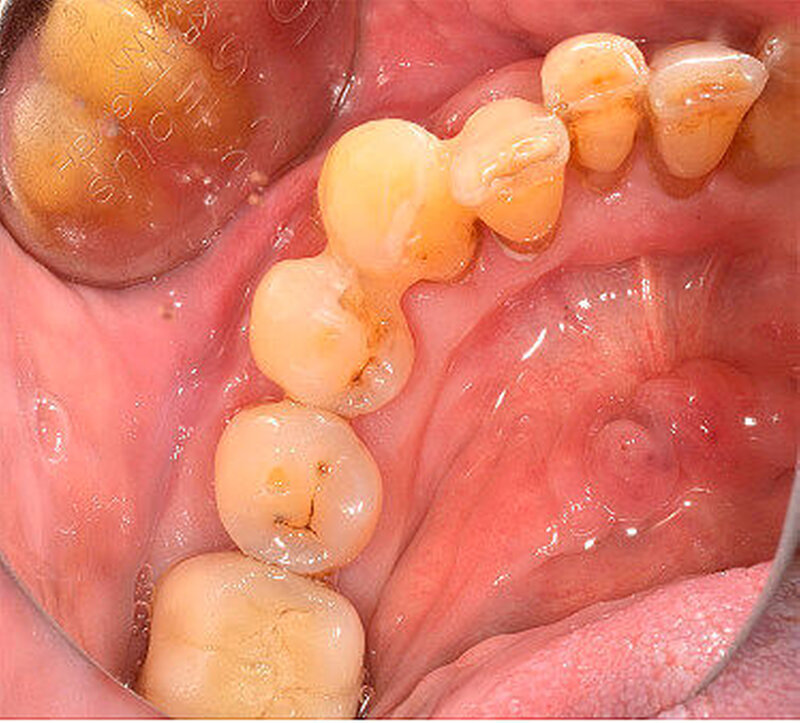

Der intraorale Befund zeigte neben einer moderat chronischen Parodontitis ein nekrotisierendes und ulzerierendes Schleimhautareal in regio 32 bis 35 (Abbildung 1). Überdies konnte eine Sondierungstiefe von 6 mm zwischen 32 und 33 sowie ein Lockerungsgrad von 1 bis 2 an den Zähnen 32 bis 34 bei positiver Sensibilität erhoben werden, wobei zumindest 2D-radiologisch kein Knochenabbau vorlag (Abbildung 2). Aufgrund des deutlich reduzierten Allgemeinzustandes des Patienten entschieden wir uns für eine stationäre Weiterbehandlung. Ein kurz darauf angefertigtes Blutbild zeigte unter anderem einen Hämoglobin-Wert von 5,2 mmol/l (Referenzbereich 8,6 bis 12 mmol/l), einen Hämatokrit-Wert von 0,24 (Referenzbereich 0,4 bis 0,51), einen Kernschatten-Wert von 40 Prozent (Referenzbereich 1 Prozent ) sowie einen CRP-Wert von 53,1 mg/l (Referenzbereich 5 mg/l).